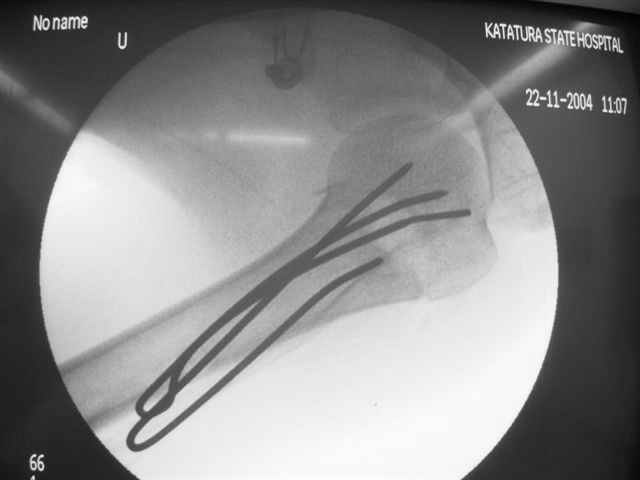

Женя, а как ты водишь спицы, в смысле, как делаешь входное отверстие, и как в него проводишь V-спицу? А то о дна из спиц, та, у которой не дошла до головки одна палочка буквы V, как-то выглядит на рентгенограмме, как будто или через очень большое отверстие введена, или каждая половинка через отдельные отверстия.

Мне кажется, проблема в том, что не все концы спиц зашли в головку, и зашедшие - недостаточно далеко прошли.

V-спица проводится через 4,5 мм отверстие. Видимо, из-за разной длины вторая половина спицы *пролетела* мимо отверстия, что и привело к вторичному смещению костных фрагментов.